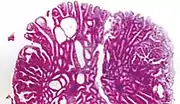

Hyperplastic polyp 0% No dysplasia.[10]

• Mucin-rich type: Serrated ("saw tooth") appearance, containing glands with star-shaped lumina.[11] Crypts that are elongated but straight, narrow and hyperchromatic at the base. All crypts reach to the muscularis mucosae.[11]

• Goblet cell-rich type: Elongated, fat crypts and little to no serration. Filled with goblet cells, extending to surface, which commonly has a tufted appearance.[11]